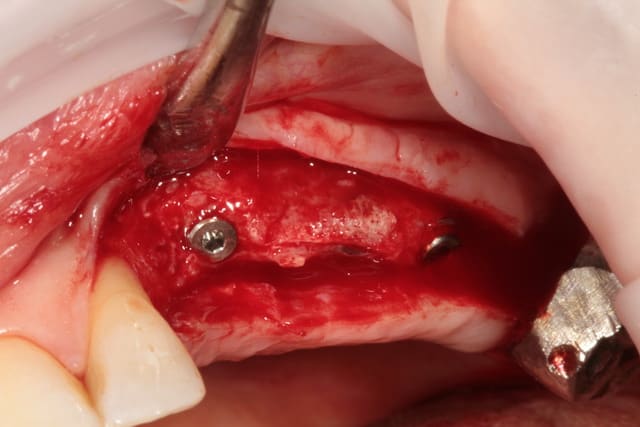

un cas récent os vestibulaire très fin.

Le lambeau avec l'os autour des implants était justement suite à un scanner ou je ne voyais pas l'os, et je voulais savoir ce que ça donnait réellement.

J'ai les scans de contrôle mais à seulement 3 ans (visibles sur d'autres post, mais sur un scan tu ne vois pas 1mm d'os autour d'un col implantaire, d'où le lambeau pour vérifier, mais je ne me vois pas faire un lambeau à tous les contrôles)) et les panos mais sur les panos on ne voit pas l'os vestibulaire.